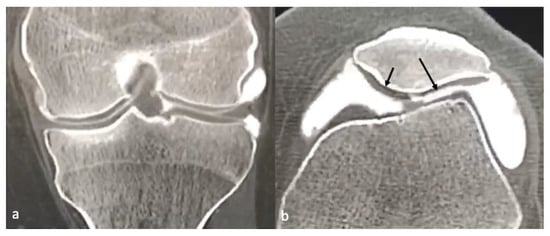

3.3. CT/CT Arthrogram

- Gorbachova, T.; Melenevsky, Y.; Cohen, M.; Cerniglia, B.W. Osteochondral Lesions of the Knee: Differentiating the Most Common Entities at MRI. Radiographics 2018, 38, 1478–1495. [Google Scholar] [CrossRef]

- Smet, A.A.D.; Ilahi, O.A.; Graf, B.K. Reassessment of the MR criteria for stability of osteochondritis dissecans in the knee and ankle. Skeletal. Radiol. 1996, 25, 159–163. [Google Scholar] [CrossRef] [PubMed]

- Kijowski, R.; de Smet, A.A. MRI Findings of Osteochondritis Dissecans of the Capitellum with Surgical Correlation. Am. J. Roentgenol. 2005, 185, 1453–1459. [Google Scholar] [CrossRef]